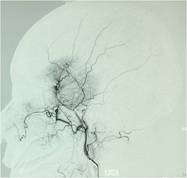

经查体,神经外六科吴杰主任诊断为:左侧蝶骨嵴占位性病变,考虑脑膜瘤可能性大。之后黄女士完善了相关检查,颅脑CT及CTA检查提示:左侧中颅窝底巨大占位病变,其内血管丰富,临近左侧大脑中动脉明显受压向上移位,考虑脑膜瘤;颅脑磁共振提示:左侧前中颅窝底巨大占位性病变,考虑脑膜瘤。介入栓塞提示:肿瘤主要由左侧脑膜中动脉额支、少量由左侧眼动脉脑膜支参与供血。

经家属同意后,医生决定栓塞肿瘤近端的供血动脉,并于当天行左侧中颅窝占位病变切除术;术中可见肿瘤灰红色,有假包膜,分块切除肿瘤;由于术前行介入栓塞,术中可见血供明显减少,且出血少,左侧大脑中动脉及左侧大脑前动脉被肿瘤压迫移位,医生给予保护后将肿瘤全切除。术后黄女士恢复顺利,已痊愈出院。病理结果显示:脑膜瘤,合体细胞型,WHO I级。

DSA显示栓塞前肿瘤主要由左侧脑膜中动脉额支供血,栓塞后肿瘤血供明显减少